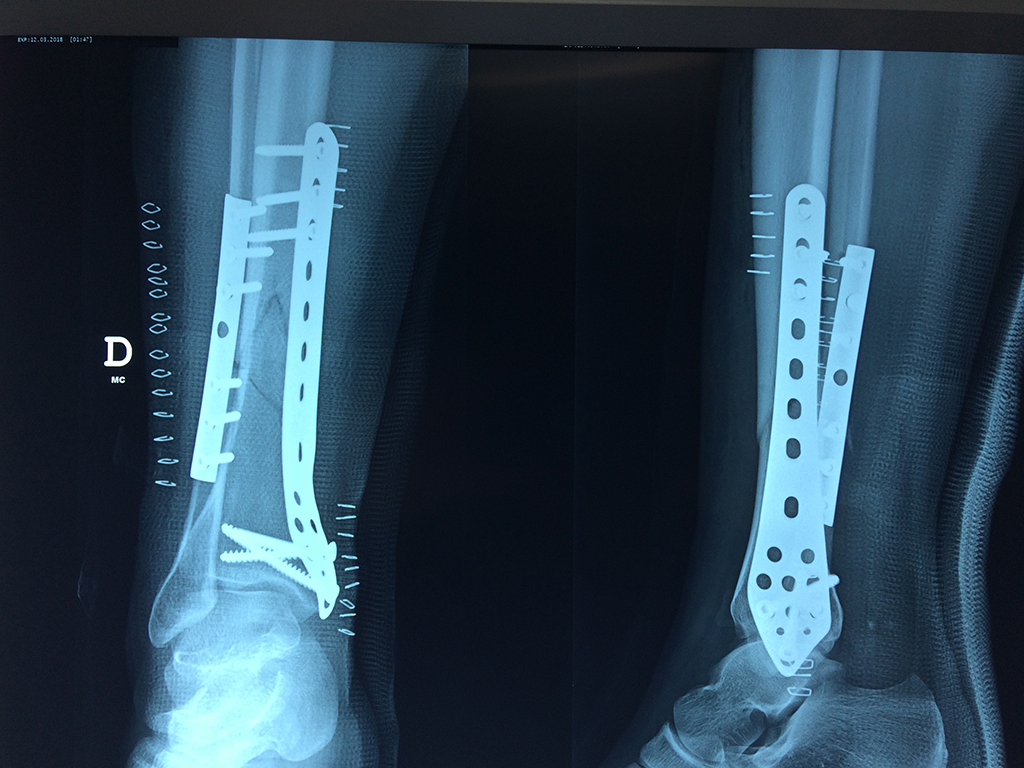

Cirugías de Tobillos

Aunque cada uno de estos huesos puede fracturarse por separado, normalmente la rotura es una lesión que se produce de forma conjunta

La mayor parte de las roturas implican a la parte proximal del hueso (parte del hueso próximo a la rodilla) o a la parte distal (parte del hueso cerca del tobillo).

Debido a la fina cobertura de piel que recubre la tibia y el peroné, las fracturas generalmente son abiertas, es decir, el hueso roto rasga la piel, atravesándola. Las fracturas de tibia y peroné generalmente se producen por un fuerte impacto o torsión.